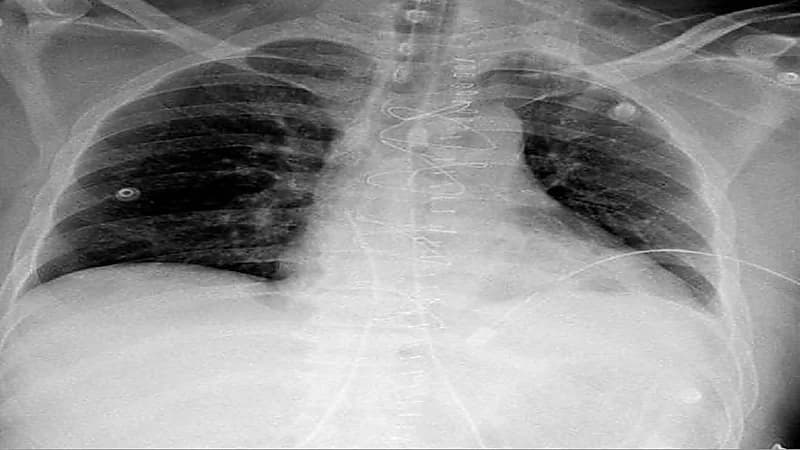

حيث تم نقله بشكلٍ عاجل لطوارئ المدينة الطبية؛ كانت حالته خلالها غير مستقرة مع هبوط في الدورة الدموية واختلال للوعي مع وجود انتفاخ في الأوردة الوداجية، بضغط يصل إلى 60/43.

وأكدت الأشعة الصوتية وجود تجمع دموي حول القلب في تجويف التامور مع وجود استرواح هوائي حول الرئة اليسرى، ليتم نقله مباشرة إلى غرفة العمليات بواسطة الفريق الطبي المكون من استشاري الإصابات د. زيسس تولوميس، وزميل جراحة الإصابات د. أحمد فلاته، وأخصائي الجراحة العامة د. أسرار الوادعي، ويترأسها استشاري ورئيس مركز الإصابات د. شرف الدين شودري.

تم فتح صدر المريض من خلال عظمة القص، وتحرير القلب من الضغط المتكون من تجمع الدم في تجويف التامور، بعد ذلك تم التحكم بالنزيف وإصلاح عضلة القلب، وبتوفيق الله تحسن المريض وغادر العناية المركزة بعد يومين وهو بصحة جيدة.